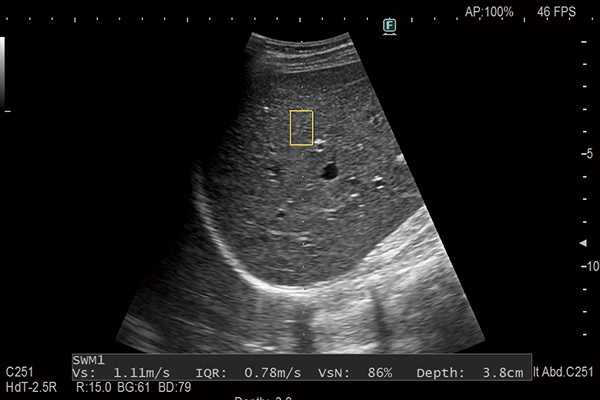

Shear waves are generated using a ‘push pulse’ to excite the tissues. SWM provides an assessment of tissue stiffness by calculating Vs, the propagation velocity of the shear waves. SWM provides an additional reliability indicator, VsN, as an objective evaluation of the Vs measurement. SWE color-codes tissue sttifness based on the propagation velocity of shear waves. SWE can be used to evaluate liver visually and non-invasively.